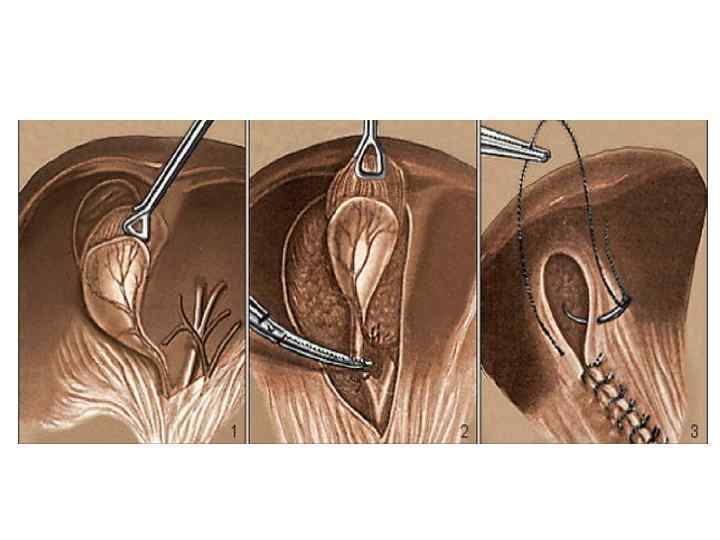

Вскрытие брюшины при ХЭ из МПД. Захват дна желчного пузыря окончатым зажимом. Субсерозное выделение желчного пузыря с помощью электрокоагуляции.

Инверсия выделенного на 2/3 желчного пузыря. Схемы дренирования после ХЭ из МПД